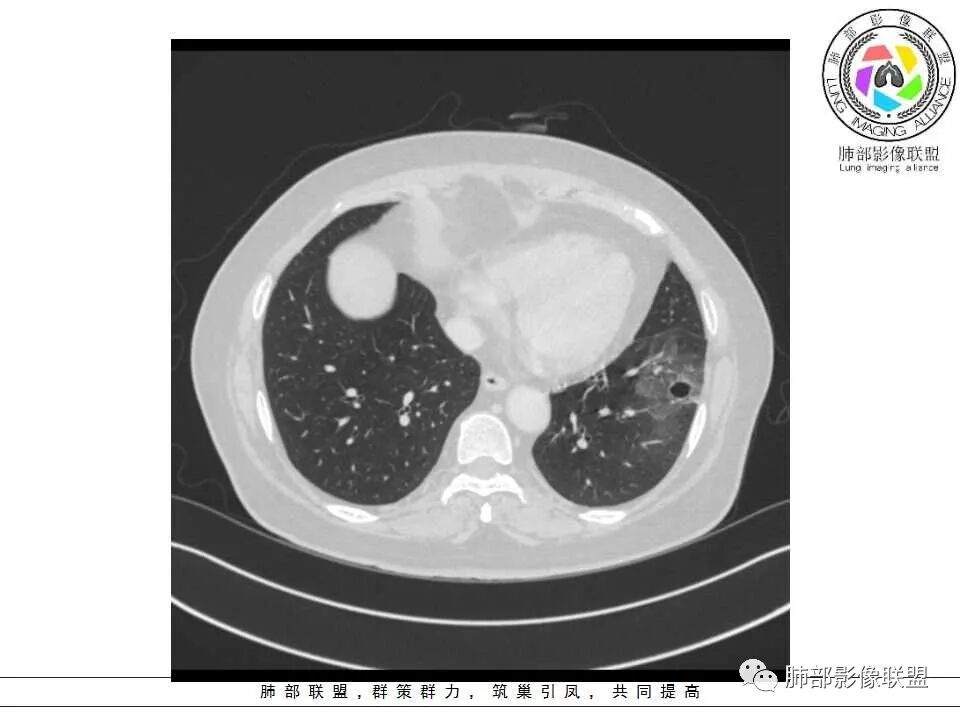

女性,65岁,咳嗽、咳痰2月余,伴发热数日。

胸CT:左肺下叶囊腔,壁厚薄不均,可见壁结节,囊腔内可见断裂小梁,部分融合,周围边界较清楚GGO,胸膜牵拉,可见血管集束、支气管充气征,冠状位部分层面可见支气管在囊腔边缘截断。考虑:囊腔型腺Ca。鉴别:肺大疱感染,CPAM等。

患者,女,65岁,2月余前受凉感冒后开始出现咳嗽,咳白痰,初发热2天,体温38℃左右,后降至正常,咳嗽无好转。近2日咳嗽加重,痰量增多,为黄白痰,无发热,无乏力、盗汗,无胸痛、胸闷,无头晕、头痛,无恶心、呕吐。PET-CT检查提示炎性病灶与恶性结节鉴别困难。

1、左肺下叶外基底段不规则囊腔样病灶,囊腔内有条形影及血管穿行。

2、囊壁薄厚不均匀,稍显僵硬,有壁结节(对应边缘分叶等)、结节强化明显。

以上两条几乎将肺囊肿彻底排除在外,且高度怀疑新生物!

3、灶周环以大范围磨玻璃影,非常均匀,没有重力分布趋势,分叶状,边界隐约可变。

4、冠状位部分层面可见支气管在囊腔边缘截断。

囊腔型肺癌主要为腺癌,少数为鳞癌。

本例囊腔性病灶尽管腔壁稍显僵硬,壁结节凸显,但女性患者,灶周明显磨玻璃晕,都强烈提示为囊腔性腺癌。

大范围磨玻璃影可以符合粘液腺癌。机制包括分泌黏液的癌细胞沿肺泡壁生长以及含肿瘤细胞的黏液成分沿气道飘散种植等。囊腔形成推测肿瘤等成分形成小支气管的活瓣阻塞所致。

周围磨玻璃影不支持炎性渗出,没有沿气道分布,边缘较清楚;未形成肺泡结节,出血也不符合,且患者临床无咯血。